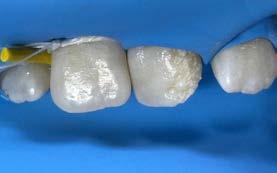

Paciente femenina de 10 años de edad, aparentemente sana, acude acompañada de su madre a la Clínica Estomatológica Tepepan, turno vespertino, de la Universidad Autónoma Metropolitana. Al examen clínico intraoral se observó el O.D. 2.1 con irregularidades en el esmalte, localizadas en los tercios cervicodistovestibular, mediodistovestibular e incisodistovestibular, con múltiples porosidades y coloración amarillenta (Figura 2).

Con base en la evaluación clínica y radiográfica, se estableció el diagnóstico pulpar de diente vital, sin signos de inflamación ni patología periapical. Asimismo, la superficie vestibular presentó integridad estructural, sin evidencia de desmineralización o lesión cariosa, clasificada como ICDAS 0 (Figura 1). Considerando estos hallazgos, se indicó un abordaje conservador mediante ameloplastia selectiva, con el objetivo de regularizar las

discontinuidades del esmalte susceptibles a la retención de biofilm.

Previo al procedimiento restaurador, se efectuó el aislamiento absoluto del campo operatorio mediante dique de hule y clamp, garantizando un entorno libre de humedad y contaminantes salivales. La zona intervenida fue desinfectada con digluconato de clorhexidina al 2% durante 60 segundos. Posteriormente, se realizó grabado ácido selectivo del esmalte con ácido ortofosfórico al 37% durante 15 segundos, seguido de enjuague profuso y secado con torundas de algodón estériles para preservar la humedad natural del O.D.

Figura 3.

Figura 4.

Se aplicó un sistema adhesivo universal según las indicaciones del fabricante y se fotopolimerizó durante 20 segundos con una lámpara de fotocurado LED de alta intensidad. La reconstrucción de la superficie vestibular se efectuó mediante técnica de estratificación con resina compuesta nanohíbrida tono A1, utilizando capas incrementales de no más de 2 mm, cada una fotopolimerizada individualmente durante 20 segundos.

Finalmente, se realizó el contorneado anatómico, pulido y acabado de la restauración, logrando una integración funcional y estética con los tejidos dentarios adyacentes (Figura 4 y 5).